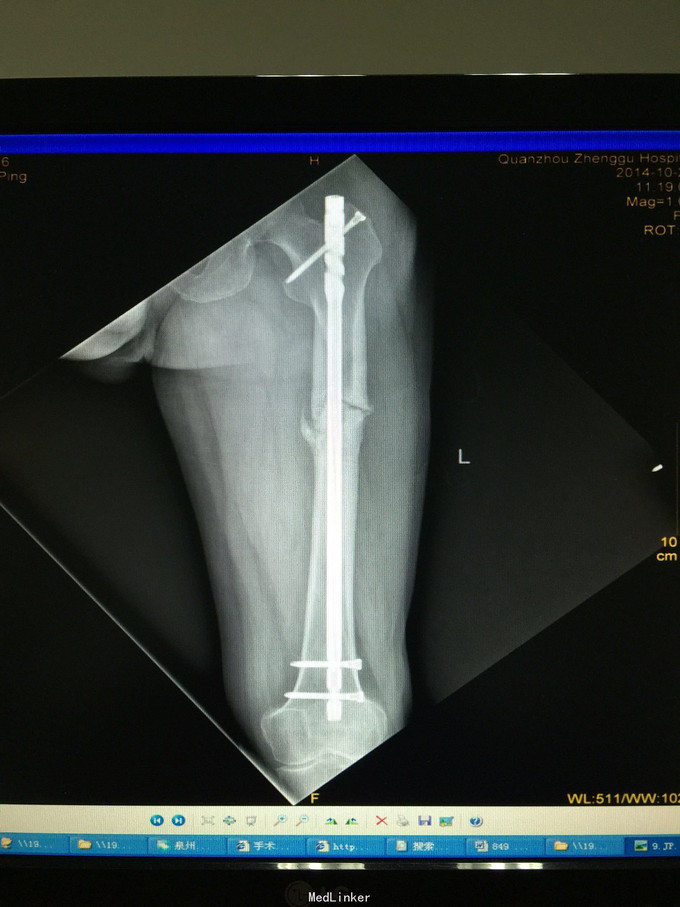

左股骨中上段骨折术后骨不连

主诉:左股骨骨折术后伴局部酸痛11个月

诊断:左股骨中上段骨折术后骨不连 处理:左股骨骨折术后骨不连断端清理+防旋钢板内固定+取髂骨植骨术

术后半年 讨论 考虑股骨中上段骨折 应力集中 近段一枚螺钉稳定性不够?